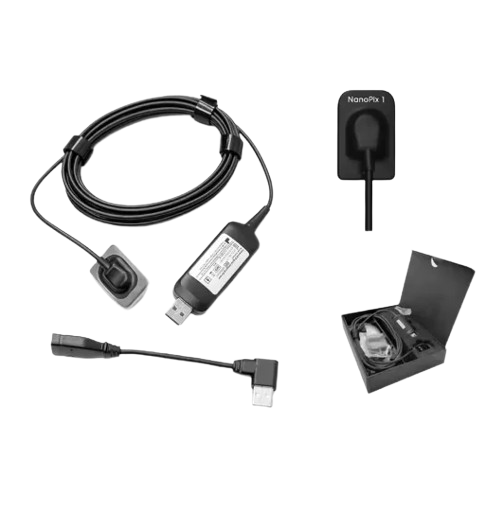

4. Comfortable Sensor Design

The sensor is designed to ensure patient comfort during scanning. Its smooth and ergonomic shape makes positioning easier.

6. Easy Integration

The Professional Dental Digital X-Ray Sensor AI-Enhanced can integrate with many dental imaging software systems for improved workflow.